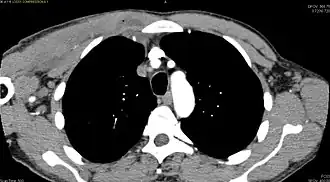

| Diagnostic method | Diagnostic method used for PM includes ultrasound, CT scan and MRI. Ultrasound can be helpful in showing muscular heterogeneity or a purulent collection but it is not useful during the first stage of the disease. CT scan can confirm the diagnosis before abscesses occur with enlargement of the involved muscles and hypodensity when abscess is present, terogenous attenuation and fluid collection with rim enhancement can be found. MRI is useful to assess PM and determine its localization and extension |

Additional images

-

CT with IV contrast showing enlargement and heterogeneous hypodensity in the right pectoralis major muscle. A focal abscess collection with gas within it is present medially. There are enlarged axillary lymph nodes and some extension into the right hemithorax. Note the soft tissue and phlegmon surrounding the right internal mammary artery and vein. The patient was HIV+ and the pyomyositis is believed to be due to direct inoculation of the muscle related to parenteral drug abuse. The patient admitted to being a "pocket shooter" -